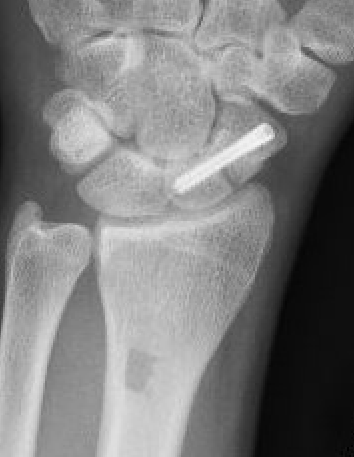

Post scaphoid ORIF

Xray

Nonunion with increased sclerosis proximal pole consistent with AVN